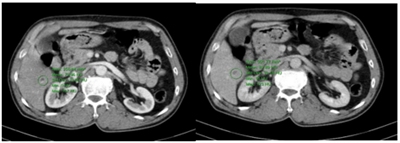

Ca lâm sàng: Điều trị đích bệnh nhân ung thư phổi không tế bào nhỏ giai đoạn muộn di căn nhiều cơ quan, tại Trung tâm Y học hạt nhân và Ung bướu – Bệnh viện Bạch Mai

Ung thư phổi là nguyên nhân hàng đầu gây tử vong do ung thư trên toàn thế giới. Trong đó, ung thư phổi không tế bào nhỏ (NSCLC) là thể thường gặp nhất, chiếm khoảng 85% các trường hợp [1]. Phần lớn bệnh nhân được chẩn đoán ở giai đoạn tiến...